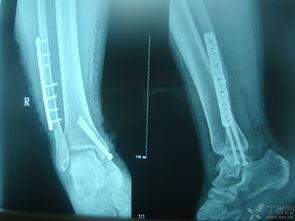

距骨,听起来是不是有点陌生?其实,它就是脚踝骨中那个小小的、形状像豆子的那块骨头。别小看了它,它可是支撑你行走的重要部分。一旦距骨骨折,那可就麻烦了,不仅疼痛难忍,连日常活动都可能受到影响。